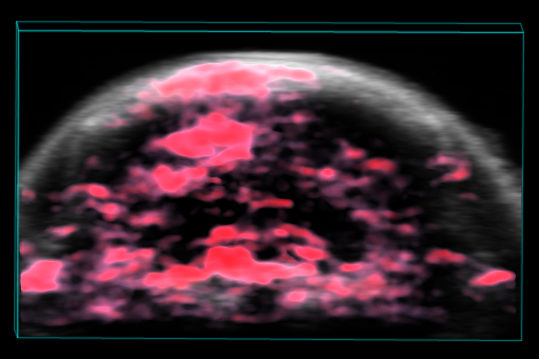

Tumor blood supply

Photoacoustic

Photoacoustic imaging allows the delivery of light energy that is absorbed by tissues causing a thermoelastic expansion. This expansion then generates ultrasound waves that are detected by the transducer and produce images of optical absorption contrast within tissues. Image in vivo tissue down to 2 cm in depth in real time and with a resolution down to 45 μm.

The Photoacoustic imaging is Non-invasive, allows to get deep, optical signals visible with high resolution and in real-time. It also allows Real-time assessment of functional data such as oxygen saturation, contrast agent distribution, pharmacokinetics and more.